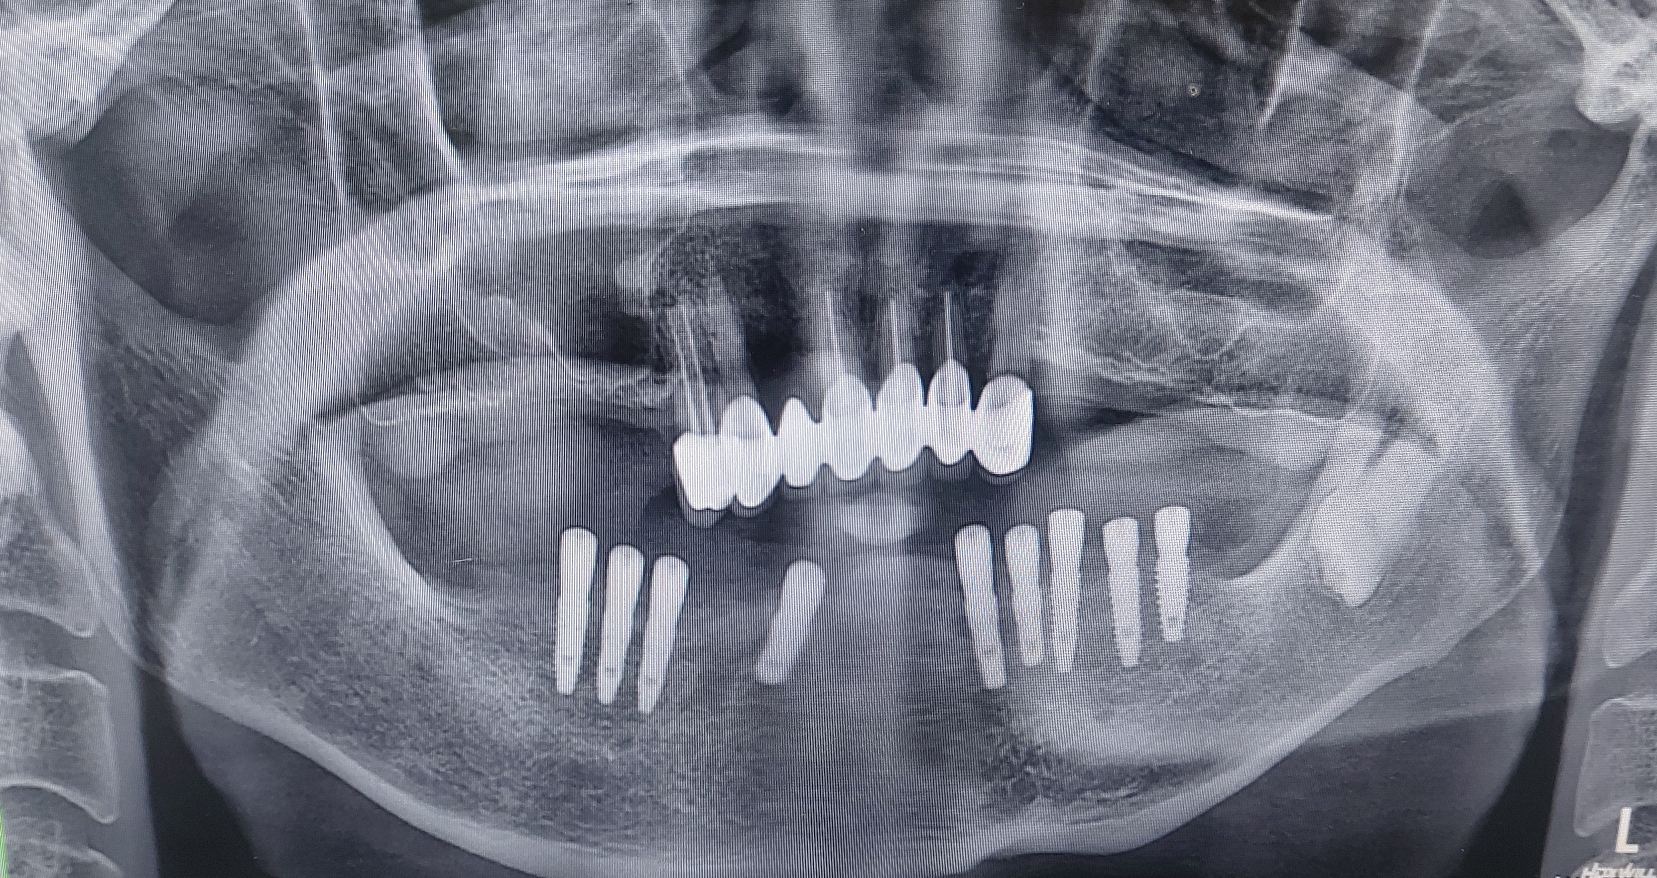

오늘 제가 수술한 환자분은 기존 타치과에서 쓰시던 임플란트 고정성 틀니의 만족도도 나쁘지 않았으나 나이가 아직 50대 후반으로 한창이신 여성 환자분이라 심미적인 이유로 고정성 치아를 원하셨고

제가 CT를 찍고 환자분께 일주일만 시간을 주시면 일주일뒤에는 예쁜 고정성 치아로 만들어 드린다고 자신있게 약속을 드린 환자분이었습니다.

심지어 임플란트를 단 4개만 심더라도 고정성으로 해드릴려고 노력하고 있습니다. 환자분이 느끼시는 만족도가 너무 차이가 납니다. 예전에는 교합력만으로 그 만족도를 가늠할려고 하였지만 그 와는 별개로 틀니를 빼고 있는 밤시간에 느끼는 무치악 스트레스도 무시 못하는 요인이라고 생각이 됩니다.

당장 비용 문제로 크게 고민 되시는 분이 아니라면 웬만하면 하악에서는 특히 고정성 치료를 권해 드리고 있습니다. 그리고 비용도 아예 일정금액으로 고정 시키고 심는 갯수는 제가 최대한 많이 식립해 드릴려고 하고 있습니다.

하악 무치악 환자분께는 어떠한 형태의 고정성 보철물의 디자인이 가능합니다.